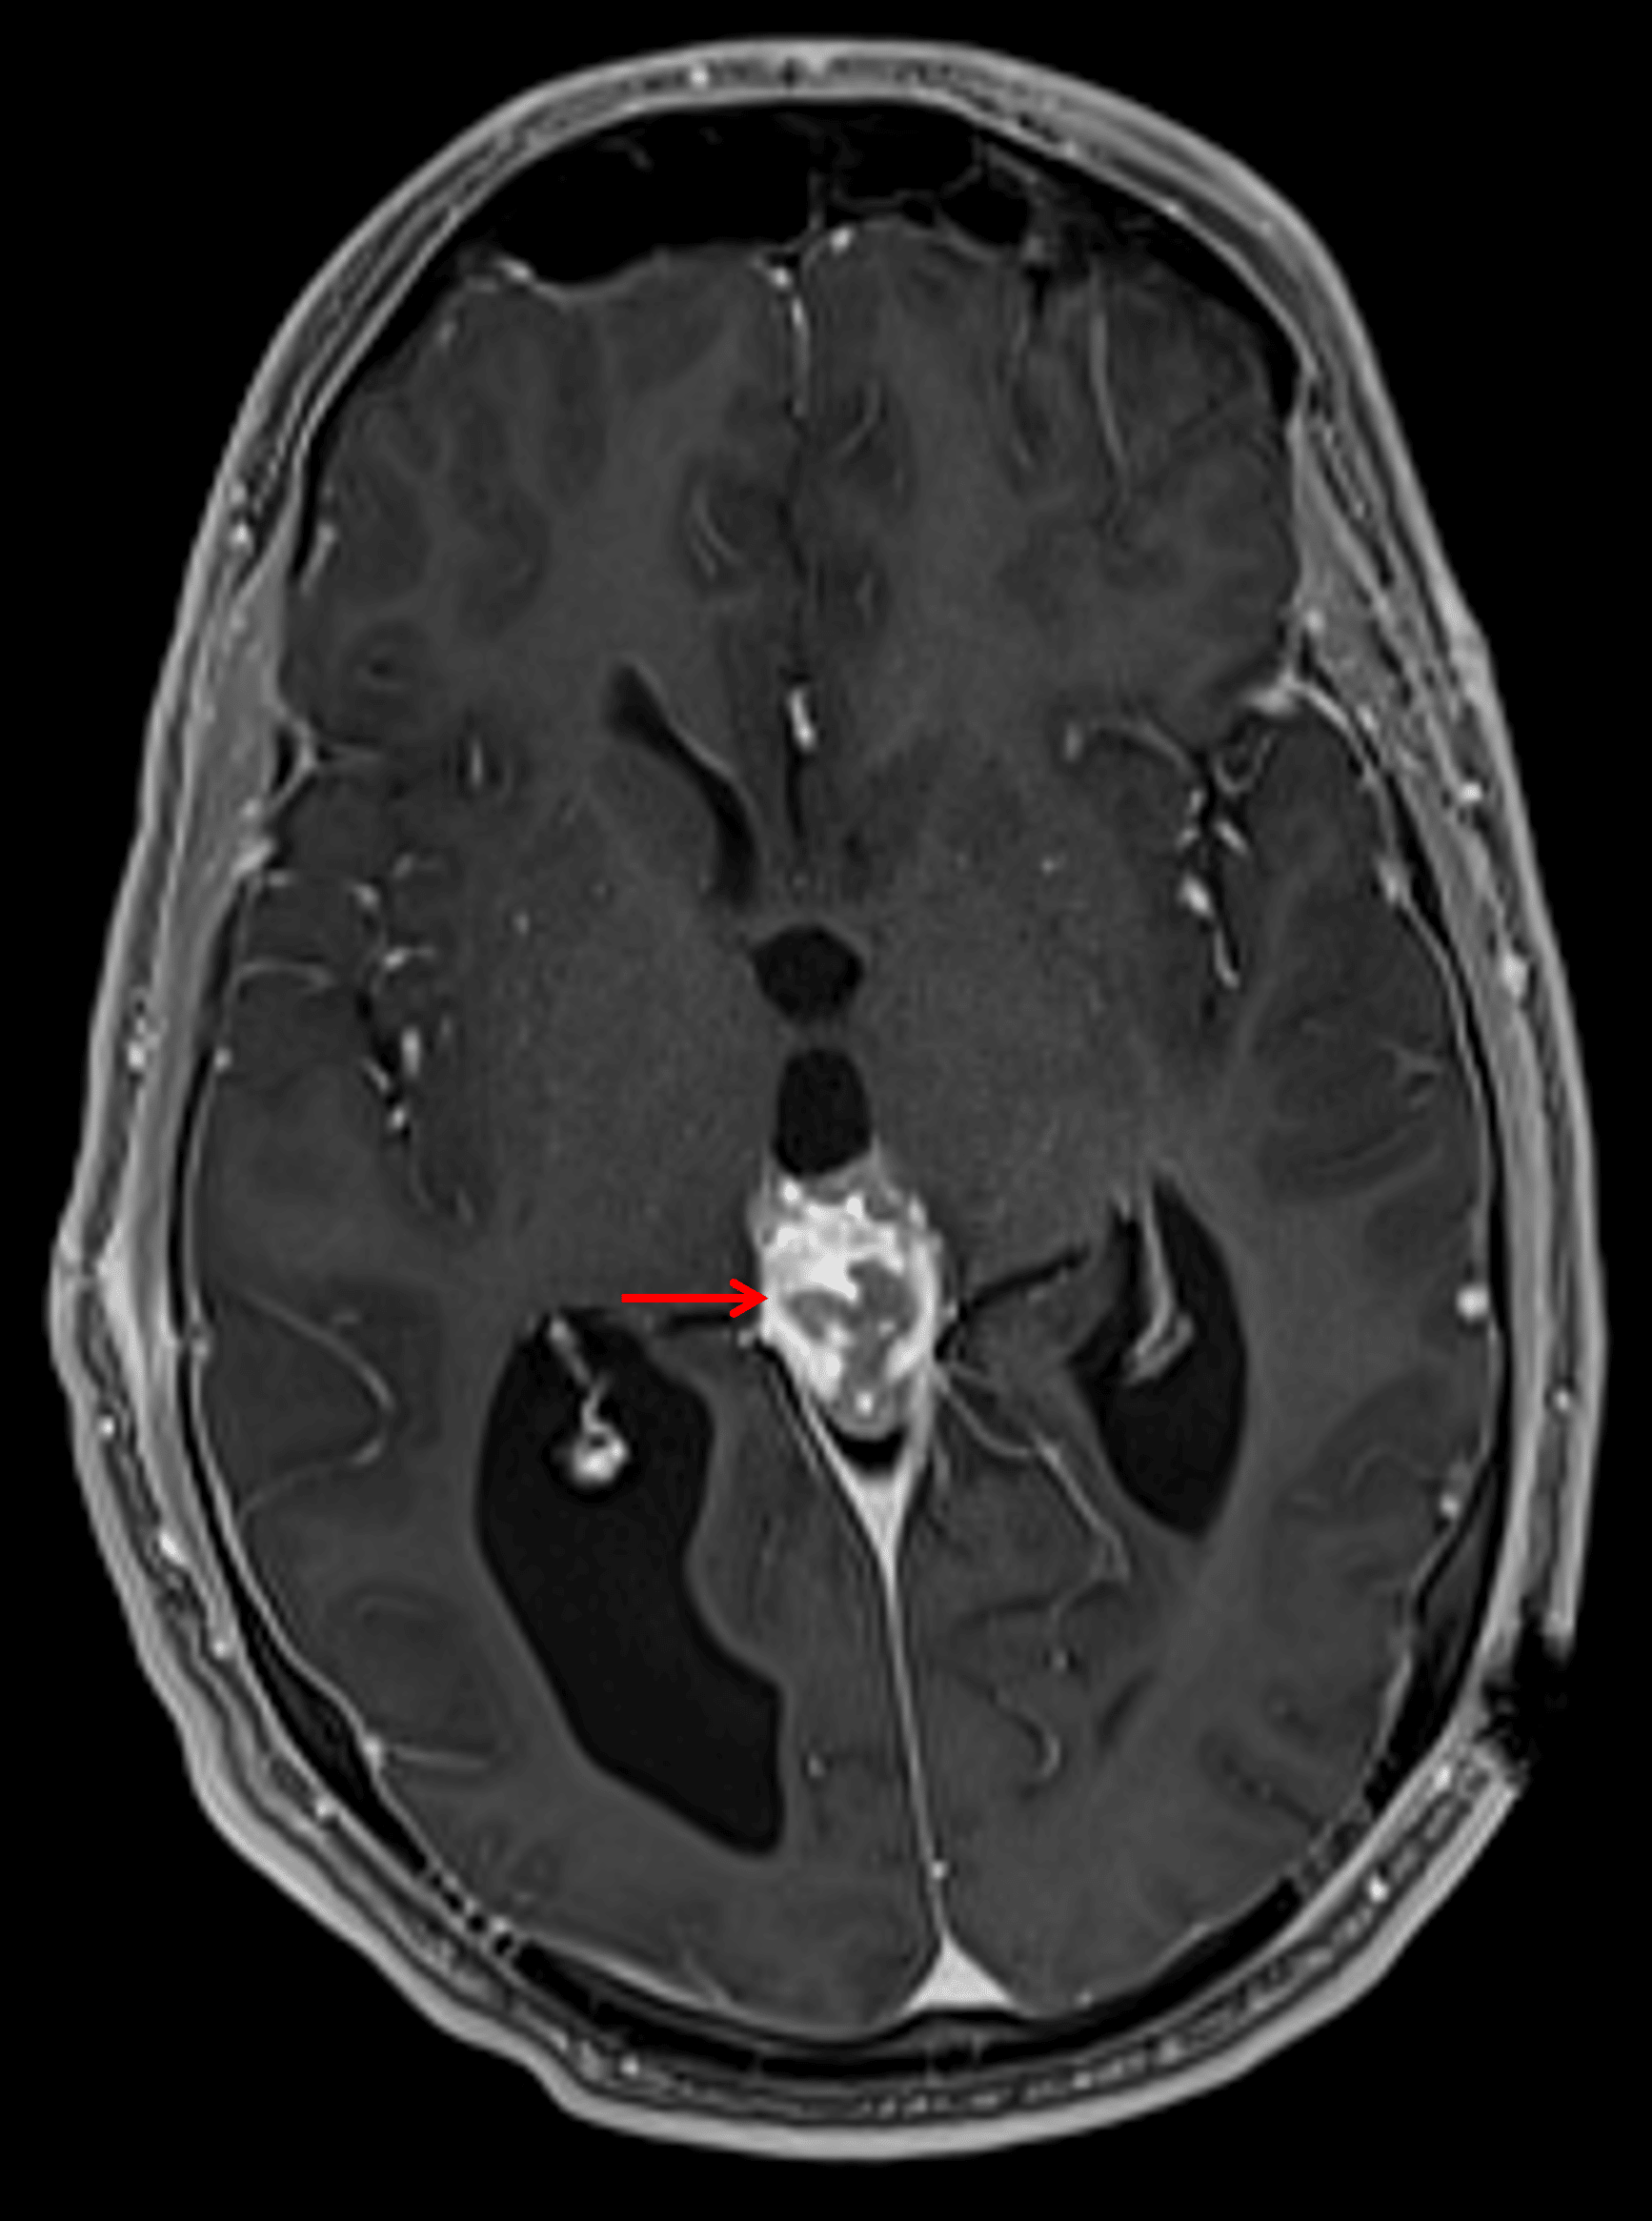

MRI

- Avidly, somewhat heterogeneously enhancing pineal region mass measuring 2.7 x 2 x 3 cm which engulfs the pineal calcification and exerts downward mass effect on the tectum resulting in obstructive hydrocephalus

- Mild corresponding T1 signal hypointensity

- T2 signal intensity and restricted diffusion are similar to gray matter

- Left frontal approach ventricular drainage catheter

Corresponding avid but heterogeneous enhancement (red arrow).